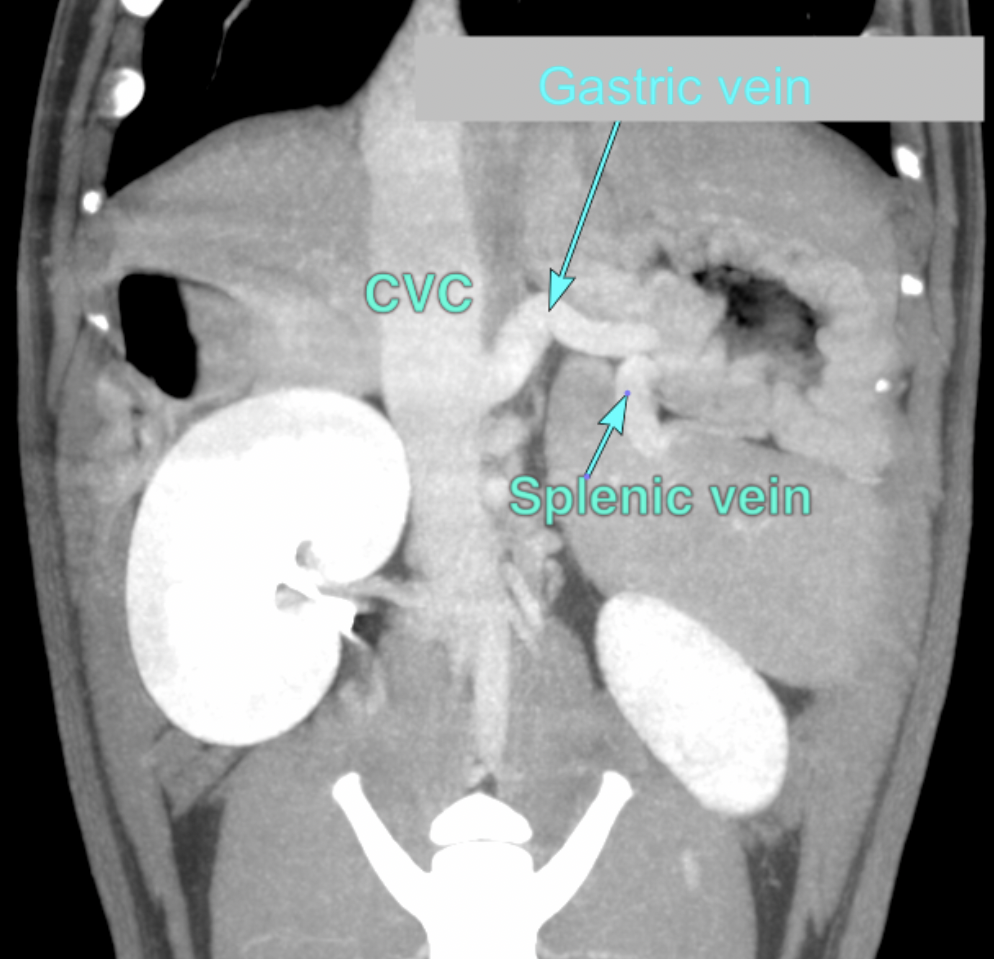

A computed tomography (CT) scan was subsequently performed, which confirmed the presence and specific location of the shunt, providing valuable information for guiding the next steps in the pet’s surgical plan.

INTERPRETATION OF THE CT FINDINGS:

- Single extrahepatic portosystemic shunt, connecting from the right gastric vein via the left gastric vein, which receives the splenic vein, to the caudal vena cava.

- An additional abnormal connection of the left pancreatic vein to the portal vein appears to be present in the region of the expected entrance location of the splenic vein.

- Associated mild microhepatia.

- Associated cystourolithiasis

The Gastroduodenal vein (GDV) and splenic vein normally empty into the portal vein (PV) separately like the above image.

In this patient, the gastroduodenal vein receives the splenic vein, is enlarged and empties abnormally into the caudal vena cava.